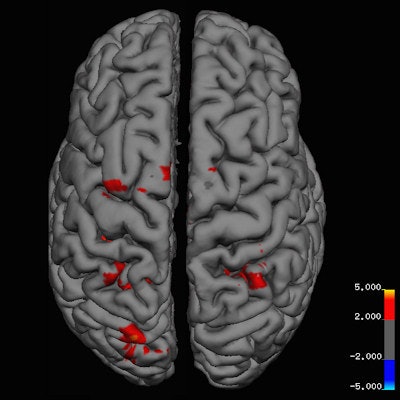

Danish researchers identified areas of heightened brain activity in people who celebrate Christmas, compared with those who have neutral feelings. All images courtesy of BMJ.MR images were obtained on a 3-tesla scanner (Achieva, Philips Healthcare), with T1-weighted magnetization-prepared rapid gradient-echo (MPRAGE) imaging for anatomical reference. Functional MRI scans used an echo-planar imaging sequence, along with cerebral perfusion through an arterial spin-labeling (ASL) sequence.

In fact, fMRI activation maps reflected five areas of heightened activity in response to holiday images in the Christmas group versus the non-Christmas group. These areas were the left primary motor and premotor cortex, right inferior and superior parietal lobule, and bilateral primary somatosensory cortex (p < 0.001).

"The left and right parietal lobules have been shown in earlier fMRI studies to play a determining role in self-transcendence, the personality trait regarding predisposition to spirituality," the authors wrote.

In addition, the frontal premotor cortex is important for experiencing emotions shared with others by mirroring or copying their body state, and premotor cortical mirror neurons even respond to observation of ingestive mouth actions.